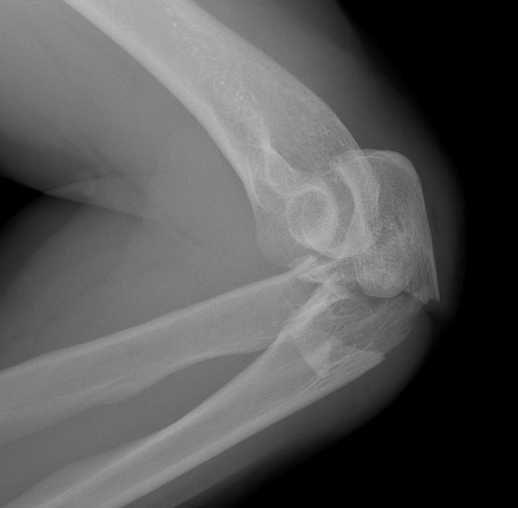

Mayo Classification

A: Non comminuted

B: Comminuted

| Type I | Type II | Type III |

|---|---|---|

| Minimally displaced | Displaced | Trans-olecranon fracture dislocation |

| 10% | 85% | 5% |